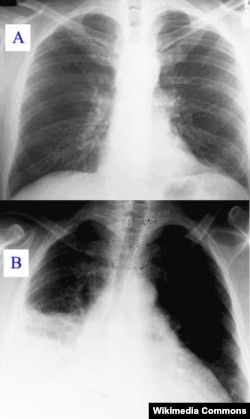

Pelaksana Tugas Direktur Jenderal Pencegahan dan Pengendalian Penyakit (P2P) Kementerian Kesehatan (Kemenkes), Yudhi Pramono mengatakan pneumonia masih menjadi penyebab utama kematian pada bayi dan anak-anak di dunia. Pneumonia adalah peradangan akut pada parenkim paru (alveoli) yang disebabkan oleh mikroorganisme, termasuk bakteri patogen, virus, jamur dan parasit.

Dokter Wahyuni Indawati, dari Ikatan Dokter Anak Indonesia (IDAI) mengungkapkan sangat penting untuk mengenali gejala pneumonia agar tidak terlambat membawa anak ke fasilitas layanan kesehatan. Gejala penyakit ini berupa demam, lemah, lesu, kurang nafsu makan dan batuk. Pada mereka yang paru-parunya sudah sangat terinfeksi, penderita biasanya mengalami ritme nafas yang lebih cepat.

“Jadi kalau kita bertemu seorang anak yang mengalami batuk yang menandakan adanya infeksi di saluran pernafasan segera perhatikan apakah anak tersebut bernafas cepat atau anak tersebut menunjukkan tanda-tanda usaha bernafas yang menunjukkan anak tersebut bernafasnya sesak,” jelas Wahyuni.